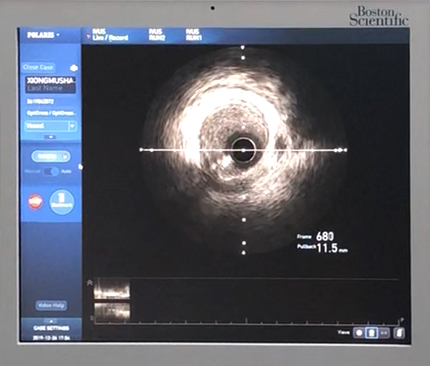

【血管内超声(IVUS)】

血管内超声是导管和超声技术相结合的产物,通过超声技术观察冠脉内壁的病理状态,如斑块纤维帽的厚度、支架贴壁情况等,还可以精确测量血管内径,使得支架的大小、长短选择更加精确,相对于X线下的影像学测量,可有效减少支架内再狭窄的发生率。